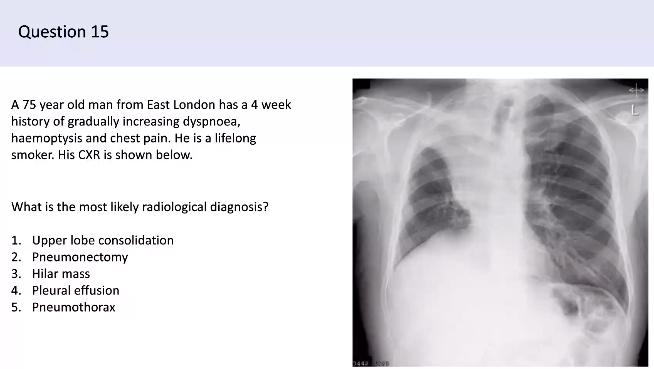

3. Hilar Mass

- Because can cause actelectasis which is what the white mass is